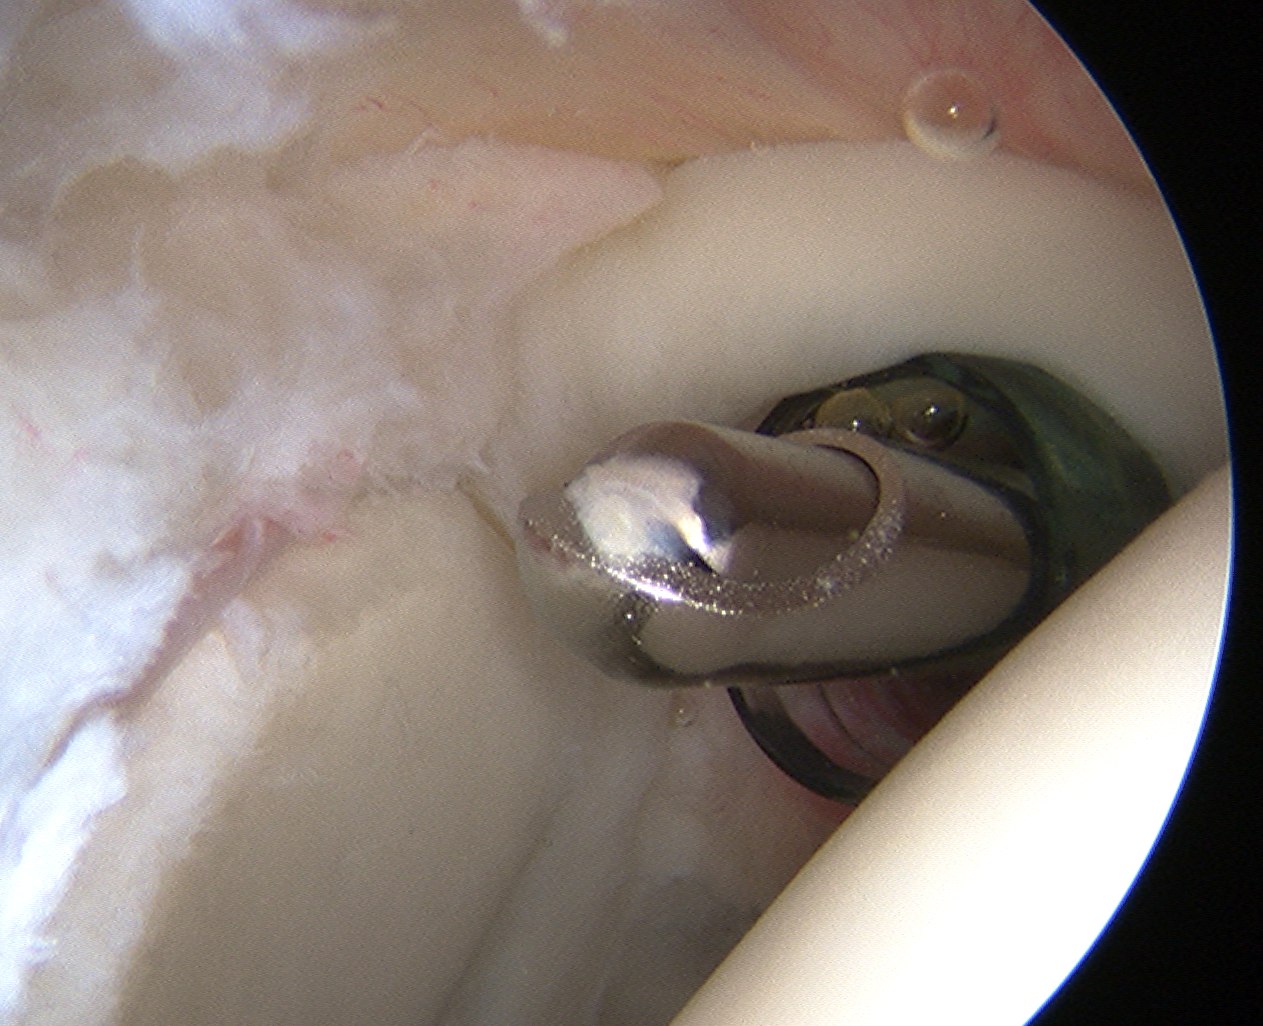

Technique arthroscopic anterior labral / Bankart repair

Steps

Mobilize anterior labrum

Debride anterior glenoid to bleeding bone

Insert minimum 3 anchors between 5.30 and 3 o'clock

Repair capsulolabral tissue

Mobilize labrum

Labral mobiliser / rasp

- labral tear can be obvious, but may have partially healed or healed medially

- change camera to anterosuperior portal for better view

- mobilize until can see subscapularis muscle underneath

- need to be able to advance labrum medially and superiorly for repair

Pass sutures and tie knots

Typically curved suture passers

Aim to tighten capsule medially and superiorly onto glenoid